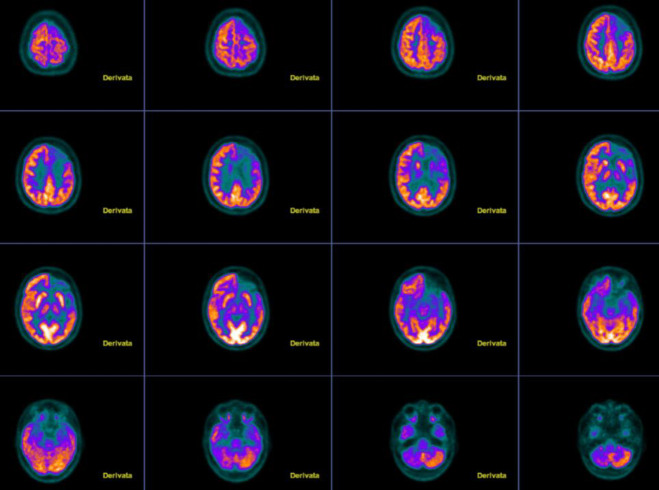

Rasmussen encephalitis (RE) is a rare condition characterized by a chronic inflammatory disorder due to unilateral inflammation of the cerebral cortex. Typically, it involves one cerebral hemisphere and manifests through intractable epileptic seizures. Its occurrence in adults is infrequent. We present a case of a 28-year-old woman who was brought to the emergency room due to the sudden onset of uncontrolled seizures. The use of 2-[18F]-FDG PET/CT (FDG-PET) helped in the differential diagnosis between autoimmune seronegative encephalitis and Rasmussen encephalitis. Even though FDG-PET is not a mandatory diagnostic criterion in the clinical evaluation of RE patients, the presented case and the available literature suggest its usefulness as a valuable diagnostic tool in patients with uncertain diagnosis, emphasizing its potential as a reliable adjunct in challenging diagnostic scenarios and for patient follow-up.